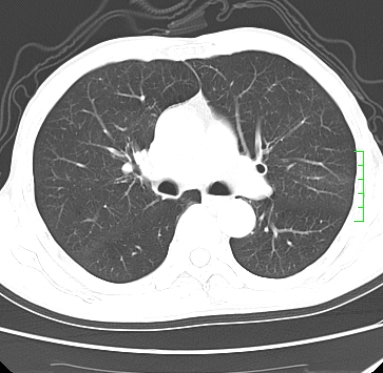

m,73y。膝关节疼痛伴双下肢水肿。入院常规胸片发现结节灶。增强为静脉期。

浅分叶、棘突,考虑右下肺周围型肺癌

考虑周围型肺癌  ,双上肺结核。

肿块周围可见局限性气肿,考虑肺癌可能性大。双肺上叶继发型肺结核。

指套征,强化明显,近侧肺组织局限性肺气肿,考虑支气管类癌,慢支、肺气肿、双上陈旧性tb、冠脉钙化。

鉴别:先天性支气管闭锁,变态反应性支气管肺曲霉菌病,肺癌,支气管囊肿,支扩黏液嵌塞。

1)考虑右肺下叶周围型肺癌。2)右肺上叶及左肺感染性病变(结核可能)。3)肺气肿。4)冠状动脉钙化。